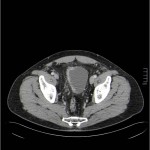

Caso 30

Efectivamente hay que hacer un URO-TC, que es un examen diagnóstico optimizado para estudiar riñones, uréteres y vejiga mediante TC multidetector empleando cortes finos, contraste IV y que incluye siempre una fase excretora, así que permite evaluar la fase portal y la fase excretora (8 minutos después de la suministración del contraste). (1,2)

¿Qué hallazgo patológico se aprecia en las imágenes?